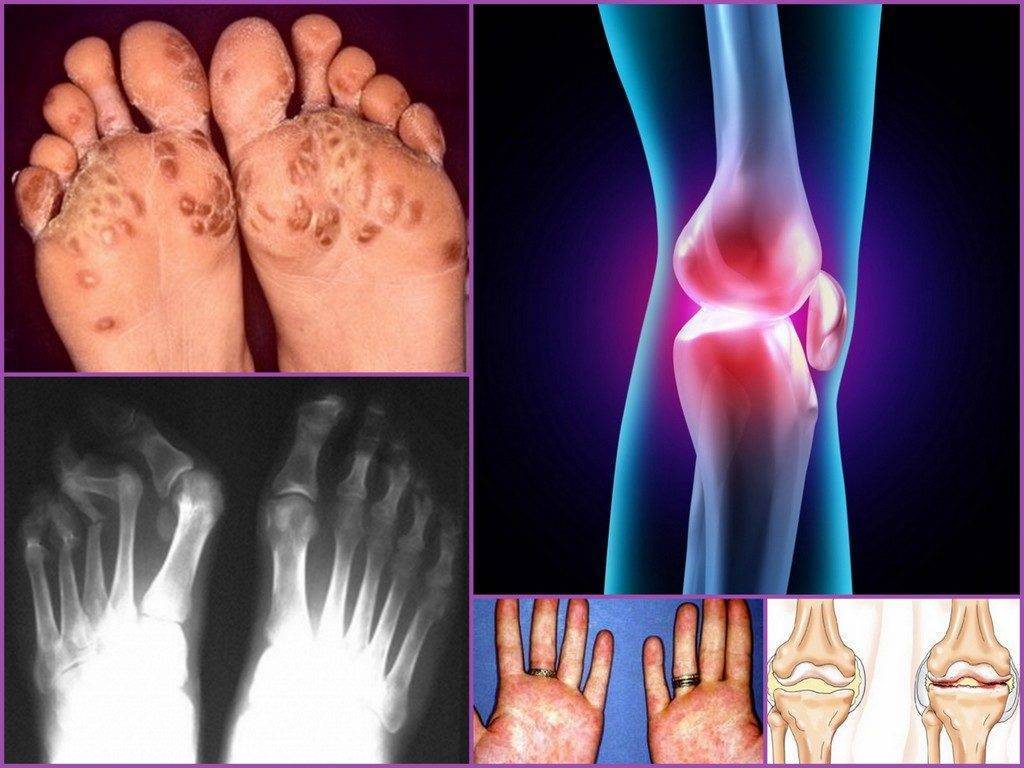

Симптомы гонита во многом зависят от формы заболевания, и в ряде случаев уже по сочетанию типичных признаков можно предположить конкретный диагноз. Но при любом виде недуга всегда отмечаются общие признаки: боль, отек, деформация и нарушение двигательной функции сустава.

ЮРА начинается остро, общим признакам гонита сопутствуют лихорадка, высыпания на коже. Типична утренняя скованность: боль и ограничение подвижности максимально выражены в утренние часы после пробуждения ребенка, а к вечеру полностью или почти полностью проходят. На коже возле колена появляются ревматические узелки. Недуг протекает хронически с периодическими обострениями, часто приводящими к необратимой деформации и потере функций коленного сустава.

Доктор Комаровский называет основными специфическими симптомами – суставные изменения:

- болезнь чаще диагностируется на тазобедренных, коленных суставах и голеностопе, значительно реже реактивная артропатия обнаруживается на других сочленениях;

- боль проявляется на левой или правой стороне, в 80-90% случаев недуг имеет асимметричное течение, двухстороннее поражение встречается редко;

- характерные клинические признаки воспалительного процесса: отёчность, боль ноющего характера (беспокоит даже при отсутствии движений конечностью), острый болевой синдром при передвижении, гиперемия, местное повышение температуры;

- хромота, может иметь преходящий характер;

- поражению могут подвергаться до 4 суставов одновременно;

- деформация пальцев, чаще поражается большой палец ноги;

- увеличение фаланг стопы.

Изменение кожного покрова и слизистой оболочки

Во время диагностики доктор обращает наибольшее внимание на кожный покров и слизистые оболочки. Нередко при наличии артрита у ребёнка или даже младенца развиваются: конъюнктивит, увеит, эрозии в ротовой полости, поражается мочеполовая система, формируется уретрит, цервицит или баланит

Рекомендация для родителей от врача – всегда стоит обращать внимание на появление сыпи на стопах или ладонях, это один из малоприметных проявлений болезни. При отсутствии лечения часто развивается кератодермия (кожа замещается ороговевшими частичками эпидермиса)

На артрит и артроз указывают:

- боли в области суставов нижних конечностей;

- дискомфорт в области крестца или поясничного отдела позвоночника;

- деформация пальца;

- хромота.

Покраснение кожи в области сустава, отек и местное повышение температуры